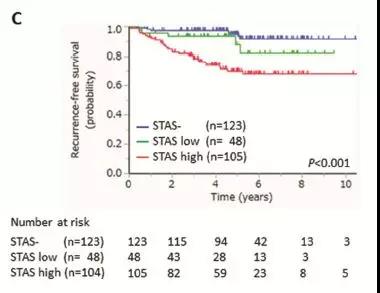

图表C:低STAS和高STAS和无STAS相比较,5年无复发生存率RFS有显著差异,无论轻微气道播散还是重度气道播散,都会导致术后5年无复发生存率降低。